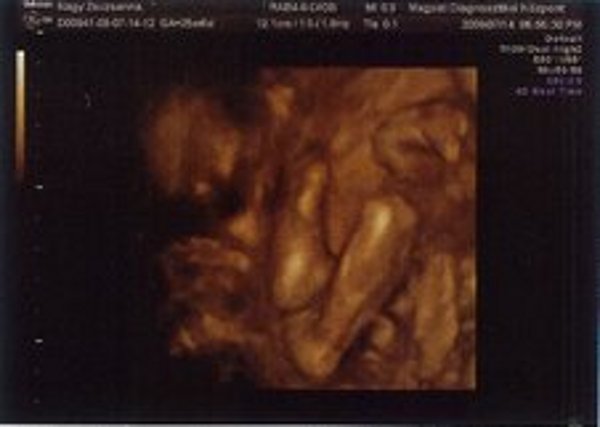

Kistörpe! Tényleg nagyon rohan az idő. Gratula Nektek! Majd hozz képet az uh-ról!